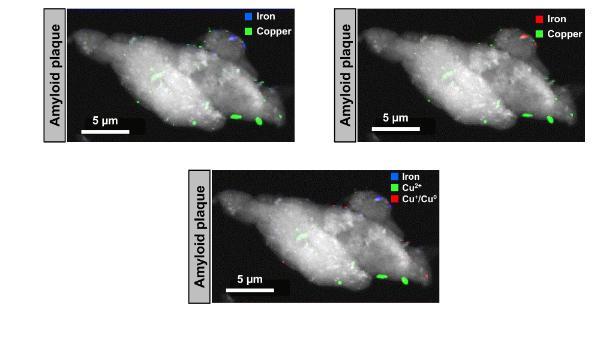

The research identified nanoscale deposits - approximately 1/10000th the size of a pinhead - of elemental metallic iron and copper in post-mortem brain tissue from patients with Alzheimer’s disease using a state-of-the-art X-ray technique called X-ray spectromicroscopy.

The identification of metallic copper and iron deposits within brain tissue indicates that metallic elements, previously observed only in microorganisms, viruses and plants, can also occur in humans. These metallic forms have distinctly different chemical and magnetic properties from the oxide forms in which brain metals are predominately stored and there are outstanding questions regarding their origins.

The team, led by scientists from Keele University in collaboration with scientists from the University of Warwick and the University of Texas San Antonio, used the UK’s national synchrotron X-ray facility, Diamond Light Source, and the Advanced Light Source in California to identify elemental metallic copper and magnetic elemental iron within the brain tissue. Synchrotrons are a form of particle accelerator which harness the power of electrons to produce brilliantly bright X-rays which can be used to study objects with exceptional chemical and spatial sensitivity. It was this unique sensitivity that enabled the nanoscale metallic particles to be observed for the first time in human biology.

Outstanding questions remain regarding the origins of the metallic brain metals, including whether they are uniquely associated with amyloid plaques or are more widely distributed throughout the brain.